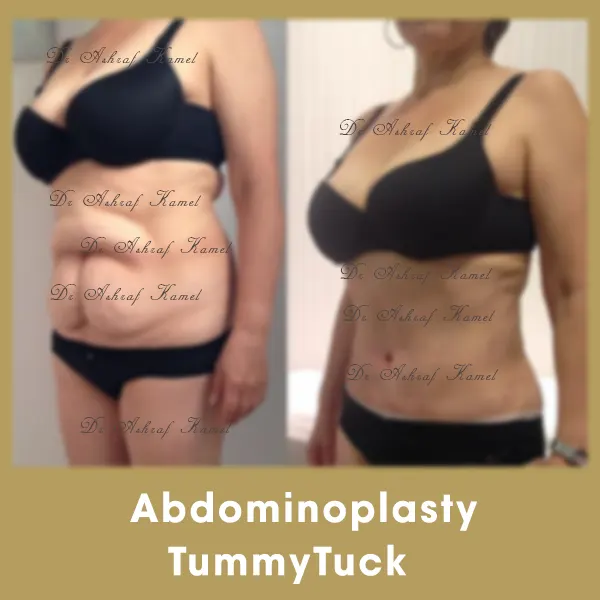

صور حالات مرضى

اشتهر بتقديم احدث تقنيات طب التجميل والجراحات التجميلية وعمليات تنسيق القوام، تكبير وتصغير وشد الثدي وتجميل الأنف وعلاج الترهلات، شد الذراعين و ازالة الترهلات، رفع الأرداف و علاج جراحات السمنة ونحت العضلات والـ6 باكس عالي التحديد، شفط الدهون بالفيزر والجي بلازما واحدث التقنيات بالخريطة الالكترونية، تجميل الجفون، تجميل الاذن وعلاج الاذن الوطواطية.